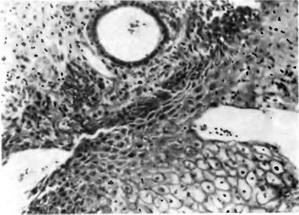

Гістологічна будова ендометріозу характеризується поєднанням залозистого эндометриоподобного епітелію і цитогенной строми. Як і в ендометрії, залози можуть мати форму трубчастих, розгалужених або мелкокистозно додаткових порожнин і вистелені однорядним циліндричним або кубічним епітелієм. Частина епітеліальних клітин має вії. Гістологічна будова ендометріозу матки та стінки піхви представлено на рис. 1, 2.

![]() Рис. 1 (ліворуч) Ендометріоз матки (гістологічний препарат); а - в товщі стінки матки: б - кістозна форма

Рис. 2. Ендометріоз стінки піхви (гістологічний препарат). |